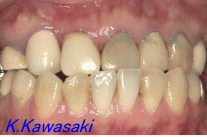

| 「前歯で物をかむことが出来ない、何とかしてほしい」と来院されました。奥歯にも虫歯が多くありました。また横顔は少し受け口でした。精密検査の結果、矯正治療後全体的に治療する事になりました。 |

| 抜歯矯正によりかみ合わせを整え、セラミックの歯を装着しました。見た目、機能の改善が出来ました。口元も美しくなりました。 |